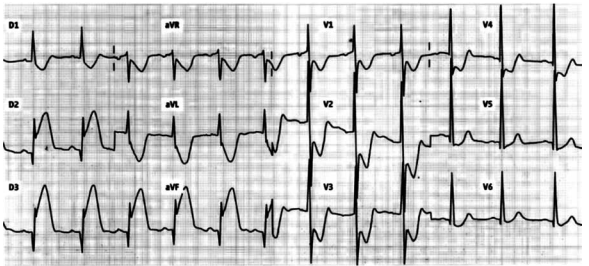

Homem, 82 anos, procura unidade básica de saúde próximo à sua residência com queixa de náuseas, vômitos e dor retroesternal de forte intensidade irradiada para membro superior esquerdo, associada a sudorese de início há 2 horas. Refere ser hipertenso, diabético e ex-tabagista. Faz uso de insulina NPH, losartana, metformina e sinvastatina. Exame físico: regular estado geral, pálido, sudoreico, PA = 80x60 mmHg, FR = 18 ipm, estase jugular bilateral. Ausculta cardíaca: bulhas rítmicas normofonéticas sem sopros; ausculta pulmonar: murmúrio vesicular presente e simétrico sem ruídos adventícios. O eletrocardiograma realizado na admissão está ilustrado a seguir.

No atendimento inicial desse paciente, além da administração de AAS e da pronta remoção para serviço habilitado para reperfusão coronária, o paciente deve receber prontamente